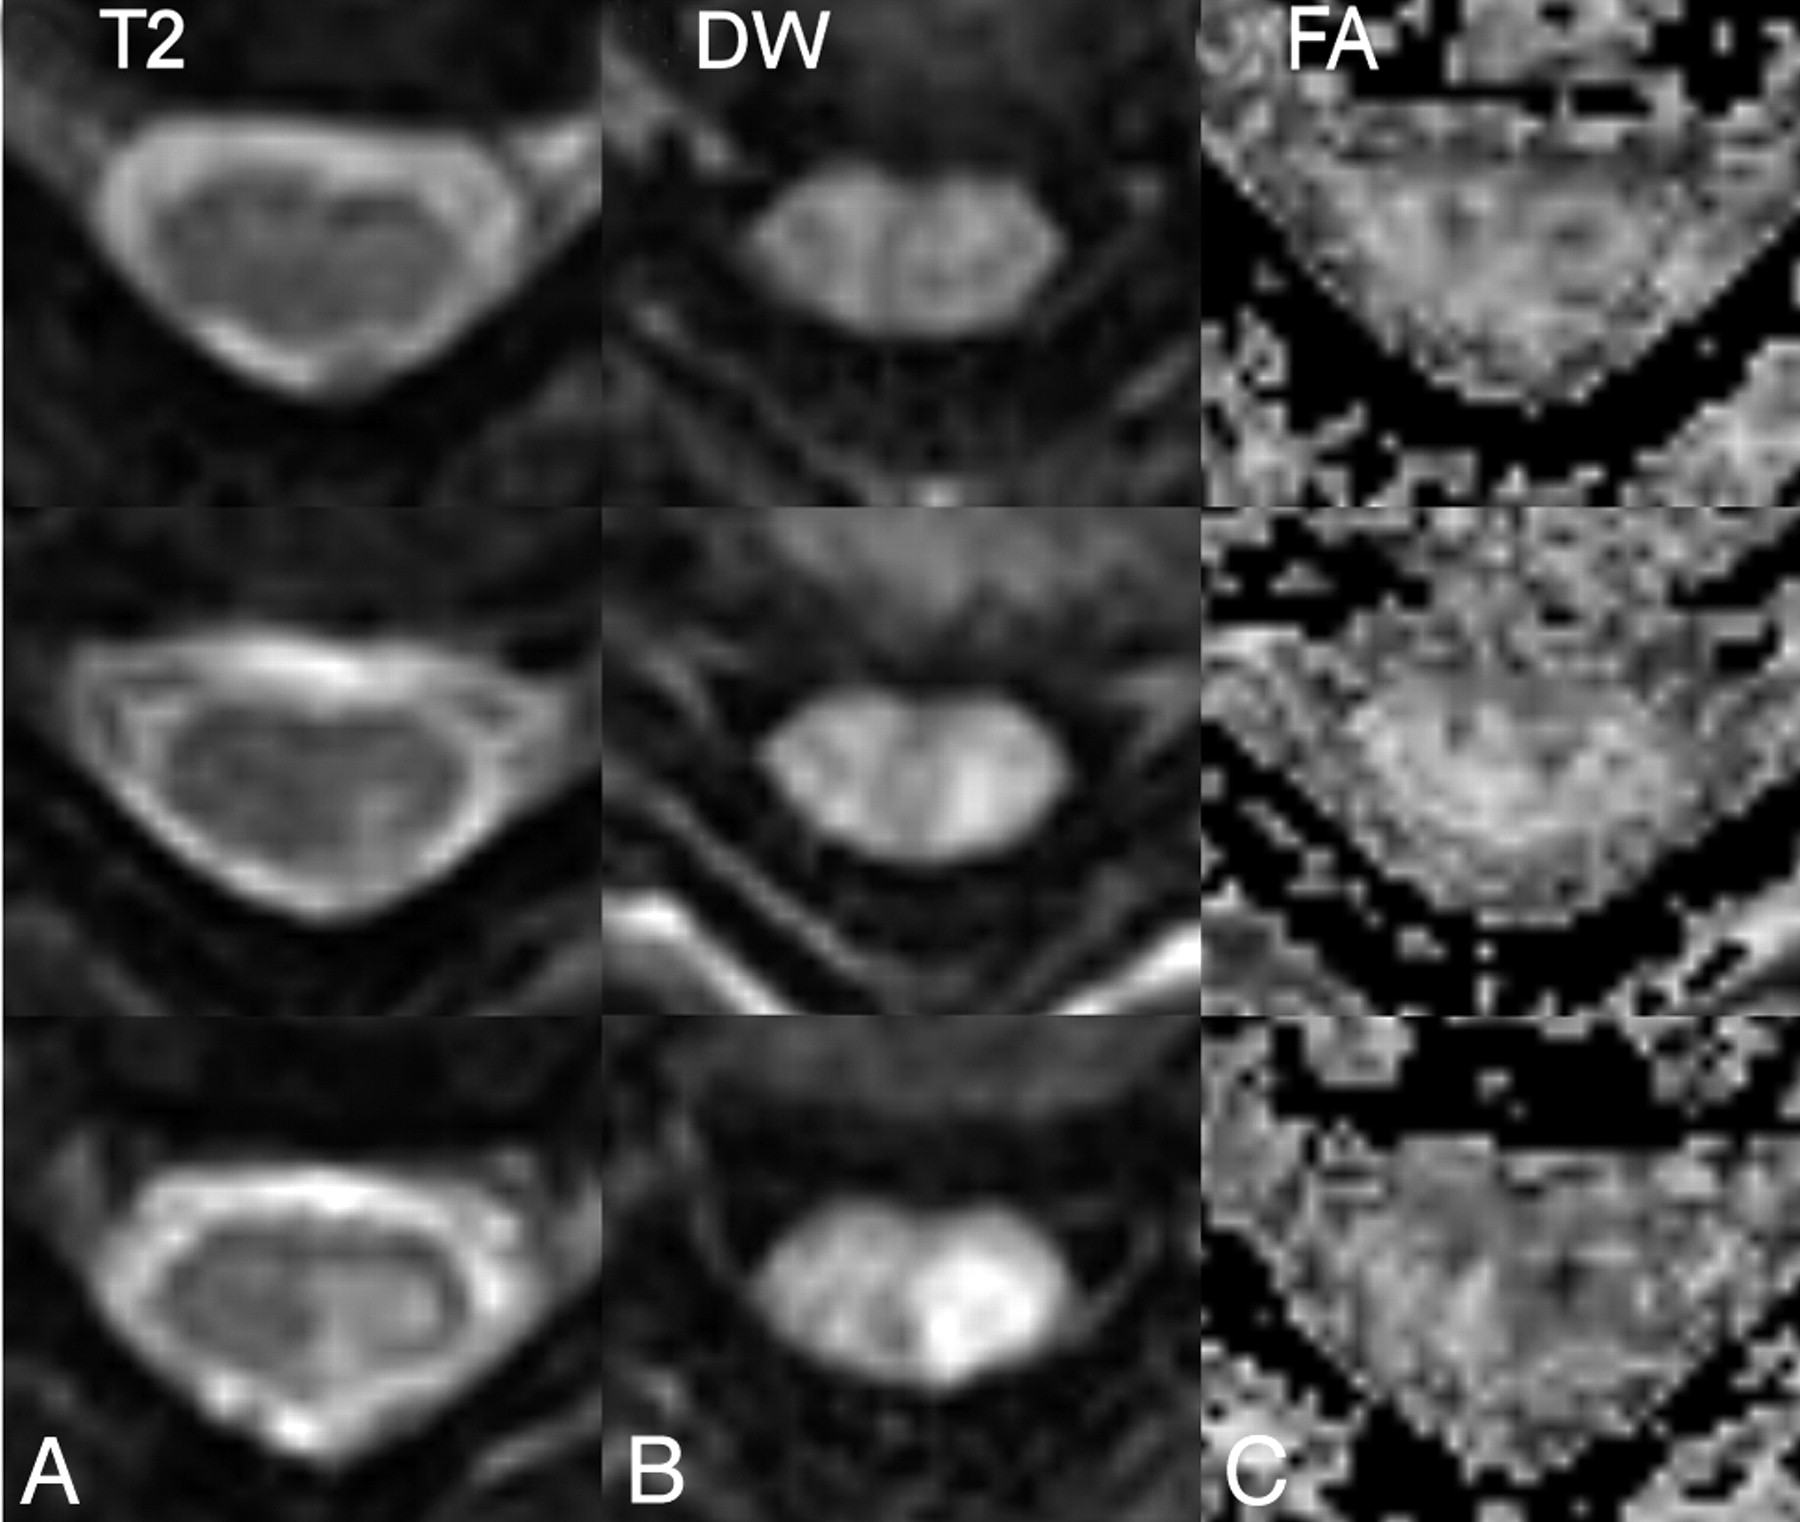

A patient with cervical syringomyelia. Axial T2-weighted images (A and D), mean diffusion-weighted images (B and E) and color-coded fractional anisotropy maps (C and F), at C2 (top row, A–C) and C3 (second row D--F) levels through the syrinx. Some residual ghosting of the spinal cord is apparent, but the orientation of the first eigenvector appears preserved. Lateral view of fiber tracking after seeding of the inferior and superior sections (G) shows little evidence of the pathology. Setting a conservative threshold on the T2-weighted images to isolate the core of the syrinx (gray), the tracks originating in the inferior section (H) and superior section (I) are seen not to penetrate this region of the pathology.

T2 (left column), and diffusion-weighted images (middle column) together with FA maps (right column) of a cervical spine lesion in a patient with multiple sclerosis. Top row, above lesion; middle row, top-most section showing T2 hyperintensity; bottom row, through widest extent of the lesion. Hyperintensity in the diffusion-weighted images follows that of the T2-weighted images, whereas in the center of the lesion is a unilateral reduction in FA.